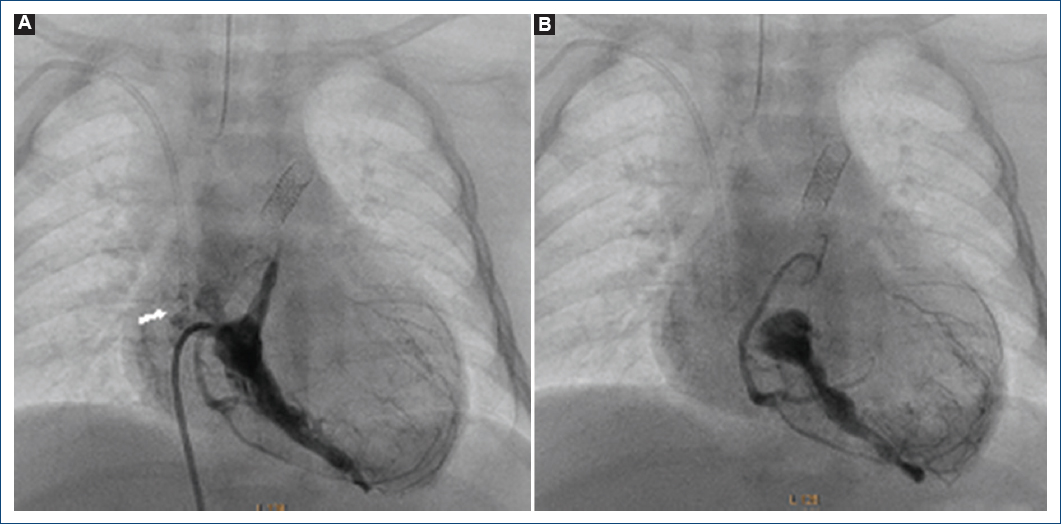

Paciente de sexo masculino de cuatro días de vida, peso 2,630 g, talla 48 cm. Cianosis desde el nacimiento, motivo de envío. Exploración física: SaO2 48%, cianosis ++++, sin soplos a su ingreso. Se inició alprostadil. ECOTT: AP-SVI, VD hipoplásico, ramas pulmonares confluentes, CIA amplia, CAP con estenosis y probables CVC. Cateterismo cardiaco: coronariografía izquierda con estenosis en el tronco coronario izquierdo y atresia en el tercio medio de la DA (Fig. 8), además de estenosis de la descendente posterior (Fig. 9A), ventriculografía derecha que confirma AP-SVI y CVC (Fig. 9B), CAP vertical. Se coloca un stent coronario no medicado 4 x 20 mm en el conducto arterioso, evoluciona de manera favorable y se extuba a las 48 horas. Su EKG sin datos de lesión o infarto (Fig. 10). Se egresa a los seis días posterior al cateterismo. A la edad de cinco meses ingresa a urgencias por cuadro de diarrea aguda con deshidratación, presenta de manera súbita irritabilidad, bajo gasto, se documenta taquicardia ventricular-fibrilación ventricular sin respuesta a maniobras avanzadas de reanimación. No se logra obtener estudio post mortem.

Figura 8 Coronariografía izquierda. A: proyección frontal: se observa el tronco coronario izquierdo con estenosis en su origen (flecha). B: proyección cuatro cámaras; flujo anterógrado de la circunfleja y atresia entre el tercio proximal y medio de la descendente anterior (flecha).

Figura 9 A: coronariografía derecha, se observa estenosis grave en la descendente posterior (flecha). B: ventriculografía derecha proyección postero-anterior, se observa atresia pulmonar con septum ventricular íntegro con conexiones ventrículo-coronarias con flujo retrógrado a la coronaria derecha y a la descendente anterior.